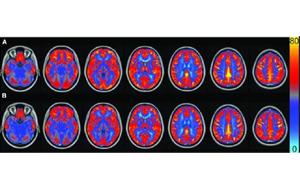

AJCN:要長(zhǎng)壽,常吃豆!長(zhǎng)期食用大豆飲食可讓大腦“更靈光”

俗話說,寧可一日無肉,不可一日無豆,俗話還說,每天吃豆三錢,何需服藥連年。作為一種理想的營(yíng)養(yǎng)物質(zhì),大豆食品在平衡膳食中至關(guān)重要??茖W(xué)家們已經(jīng)發(fā)現(xiàn),大豆具有幫助減肥、美化皮膚、預(yù)防生活習(xí)慣病、防止骨質(zhì)疏松癥等重要作用,然而,目前尚無關(guān)于大豆在調(diào)節(jié)大腦血管功能方面的研究。